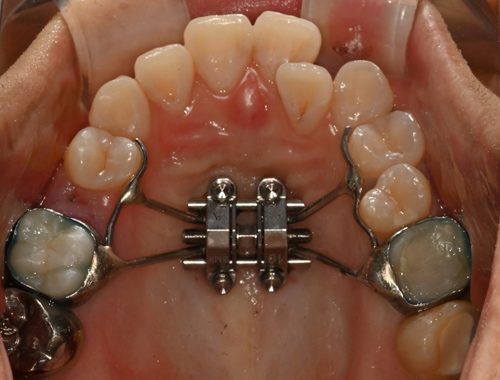

비수술 악궁확장 치료 MARPE (Miniscrew-assisted rapid palatal expansion)

덧니의 근본적인 원인은 치아 크기에 비해서 뼈의 크기가 작기 때문입니다.

청소년기가 지나간 성인에서는 뼈의 크기를 늘리기 어렵지만 이지민 대표원장은 가능합니다.

이지민 원장은 성인 비발치 교정의 핵심인 비수술 악궁 확장 가능성을, 직접 연구한 논문 결과를 바탕으로 사전에 정밀 분석·예측합니다.

이 연구들은 현재 연세꿈꾸는치과의

교정 프로토콜에 적용되고 있습니다.